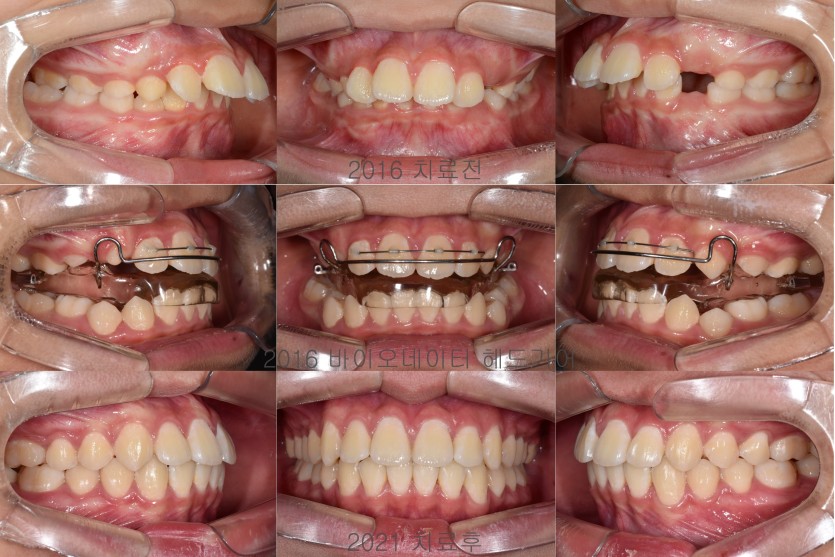

무턱의 성장조절 치료 130회

무턱을 지닌 청소년 환자들의 경우에는 안면 골격의 성장조절 치료를 진행할 수 있습니다.

사춘기는 성장이 급속하게 일어나는 시기이므로 상악의 성장을 헤드기어라는 장치를 통해 제한하고

바이오네이터라는 장치로 하악의 성장을 유도합니다.

2년 정도의 장기간 치료가 필요하며 그 기간동안 성실하게 장치를 착용해주어야 합니다.

헤드기어의 치료는 예측 가능하며 협조가 충분할 경우 상악의 성장 제한을 기대할 수 있으나

바이오네이터는 치료 반응이 좋을 수 있는 안모인지를 분류해야하며

하악의 성장이 적극적으로 일어난다기보다는 치조골의 변화를 통해 안면 골격의 편차를 극복하는 방법입니다.